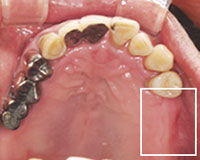

治療前の上の歯

右上の奥歯と左下の奥歯を失っているので、抜けた部分にどんどん歯が倒れかかっていき全体の歯並びを大きく崩し物を咬めない状態。キチンとかみ合わせる大黒柱がない。